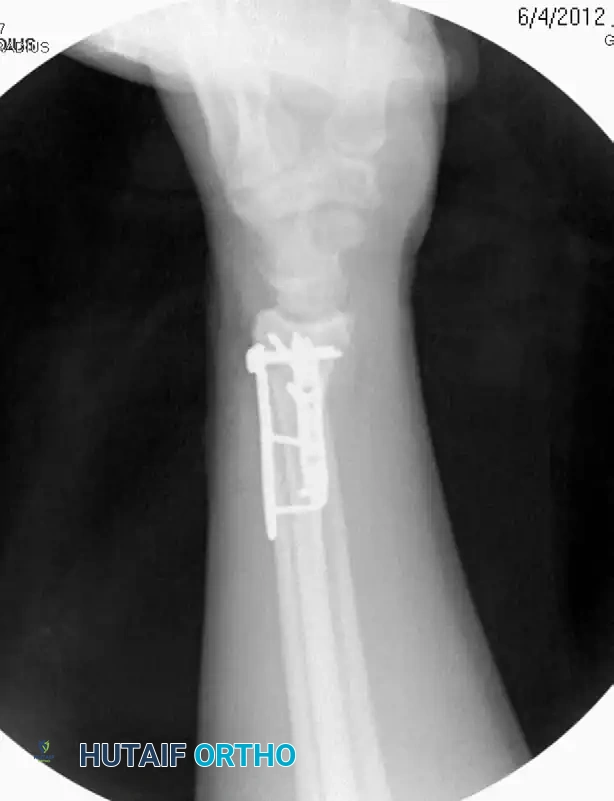

Image

The L-plate provides a volar buttress to the volar rim of the lunate facet, yet allows fixation to the subcutaneous radial side of the proximal fragment, minimizing tendon abrasion.